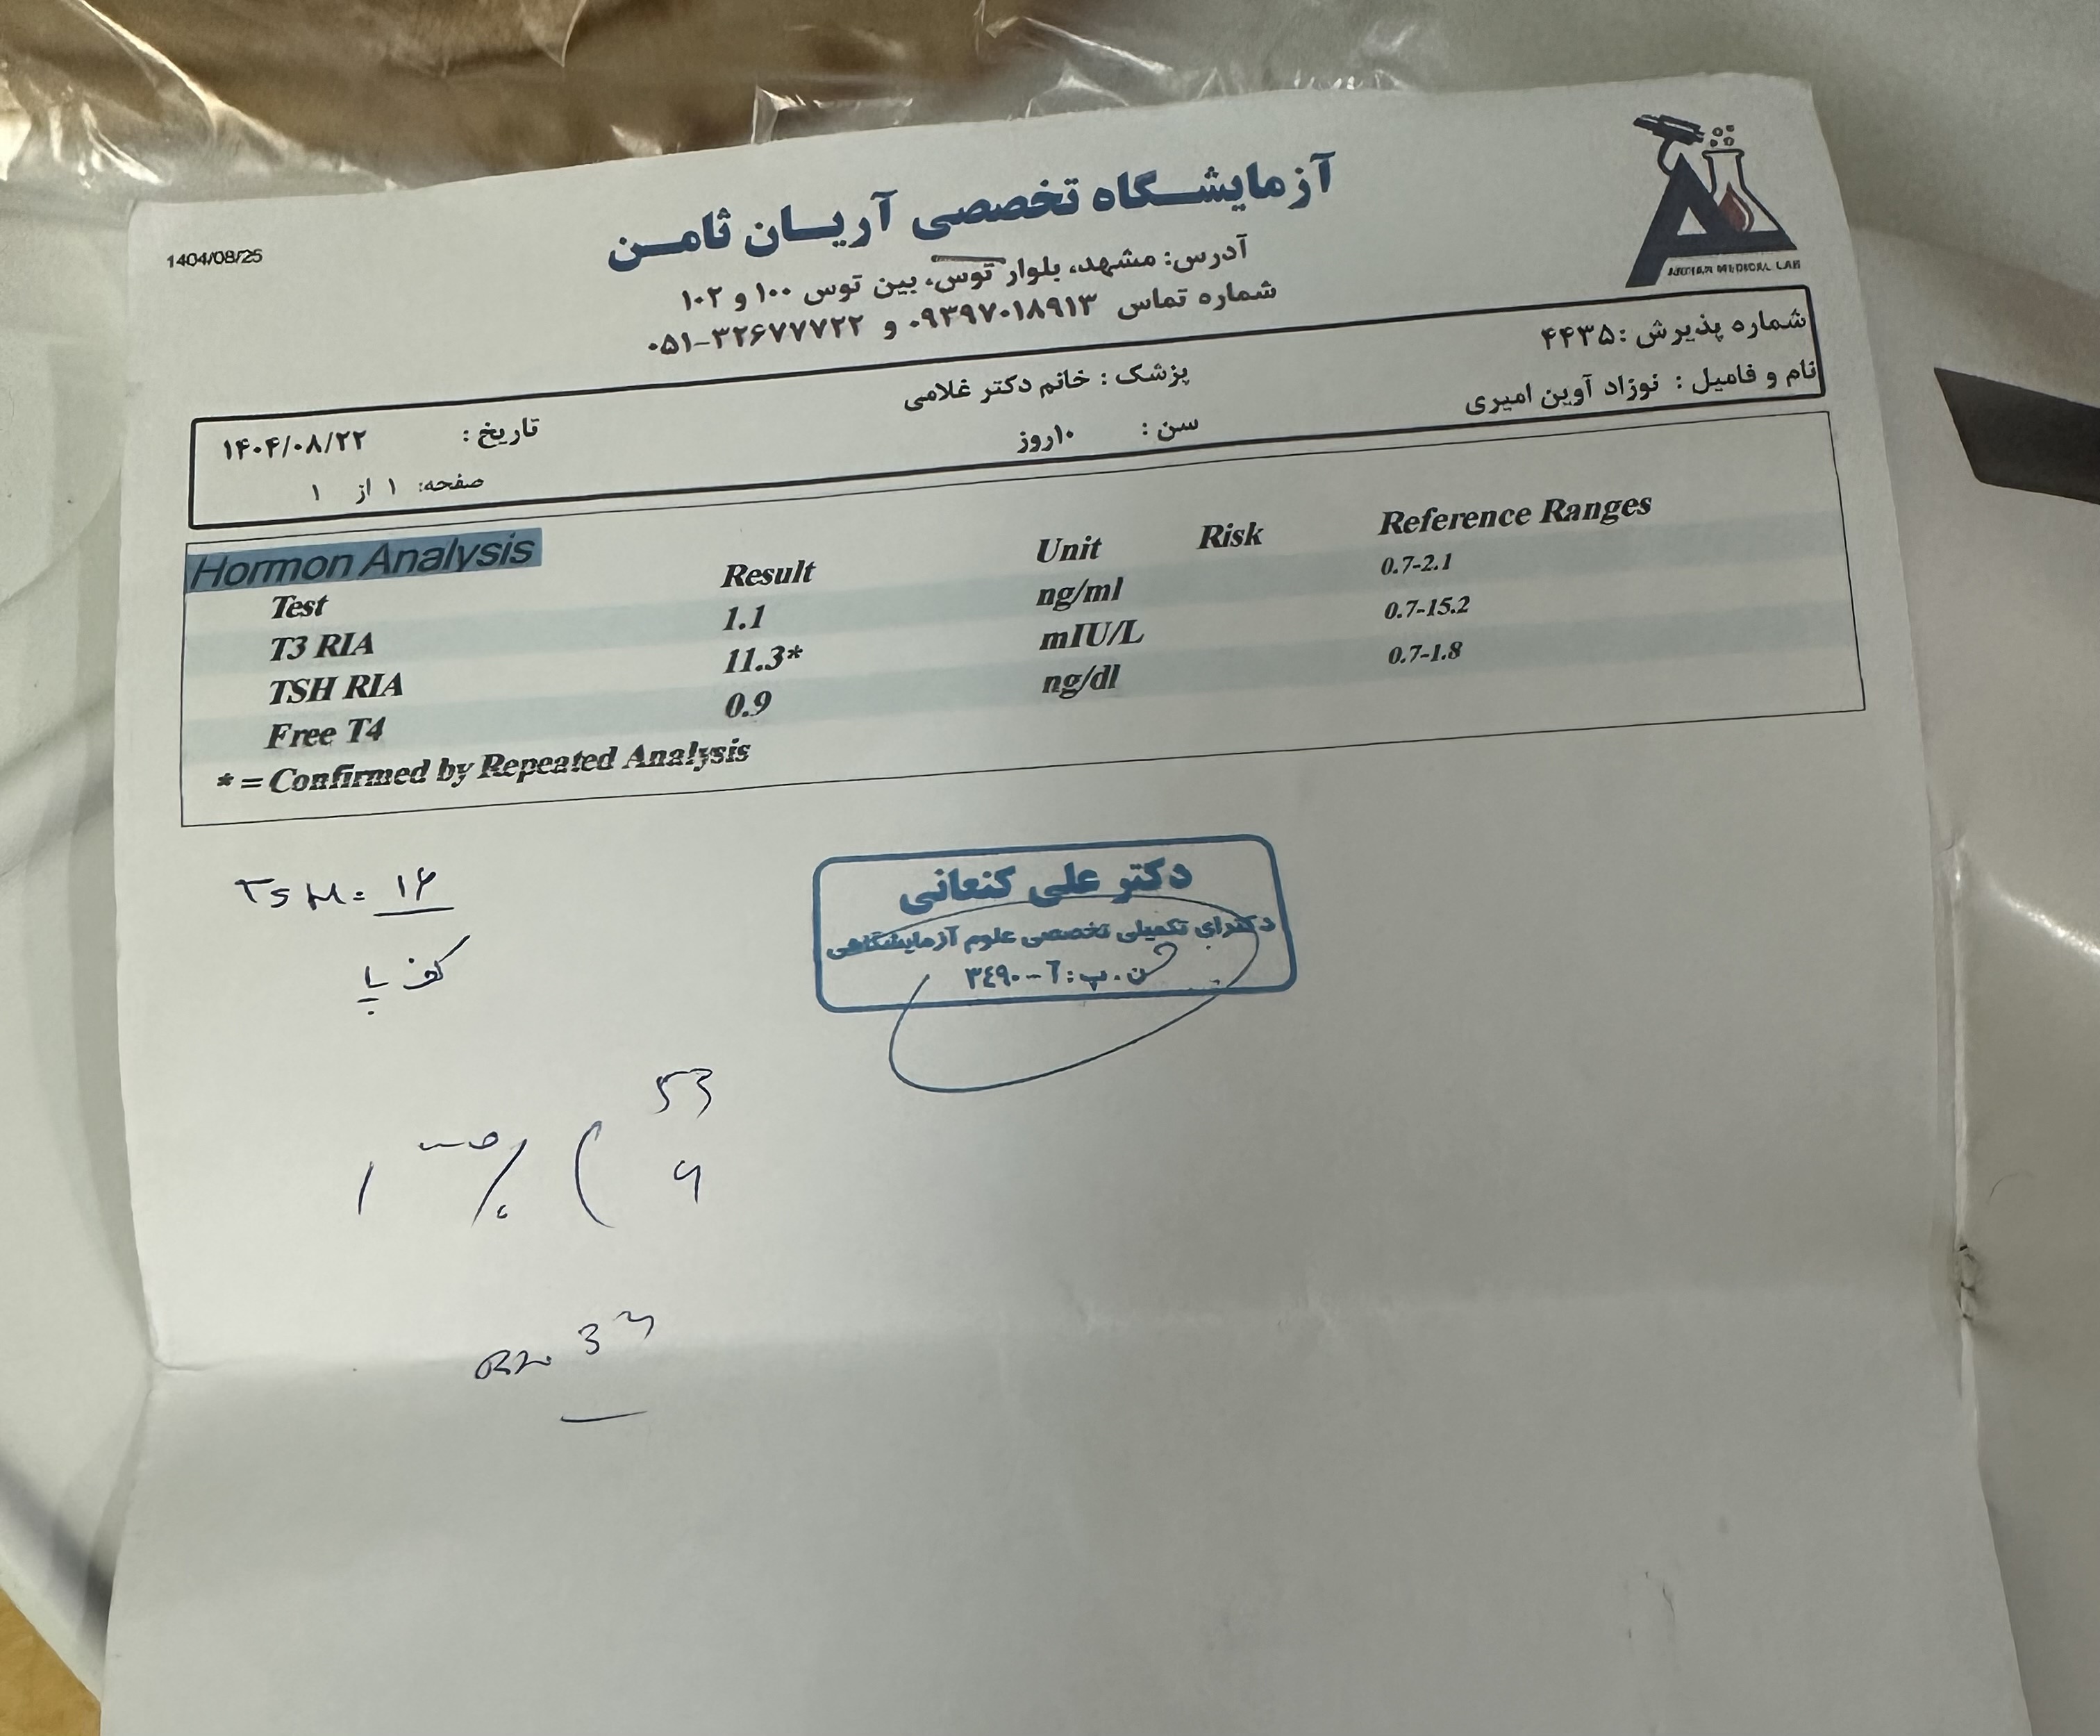

هایپوتیروئیدی

برای این کیس هنوز آزمایشی ثبت نشده است.